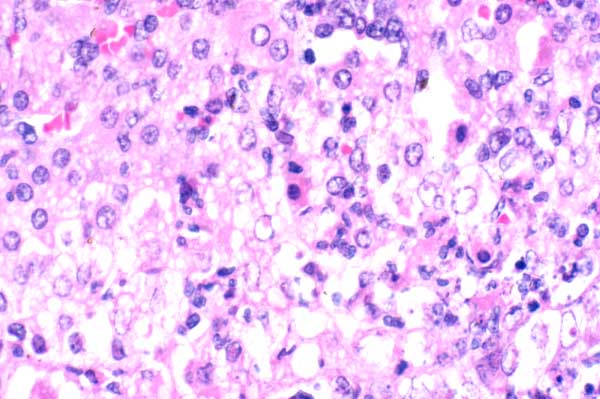

| 40x   |   Hematoxylin and Eosin | ||||

A few adrenal cortical cells are shrunken, with intensely eosinophilic cytoplasm and a pyknotic nucleus (necrosis)(arrows). Remaining cortical cells are swollen with vacuolated cytoplasm (degeneration). There are a few neutrophils.